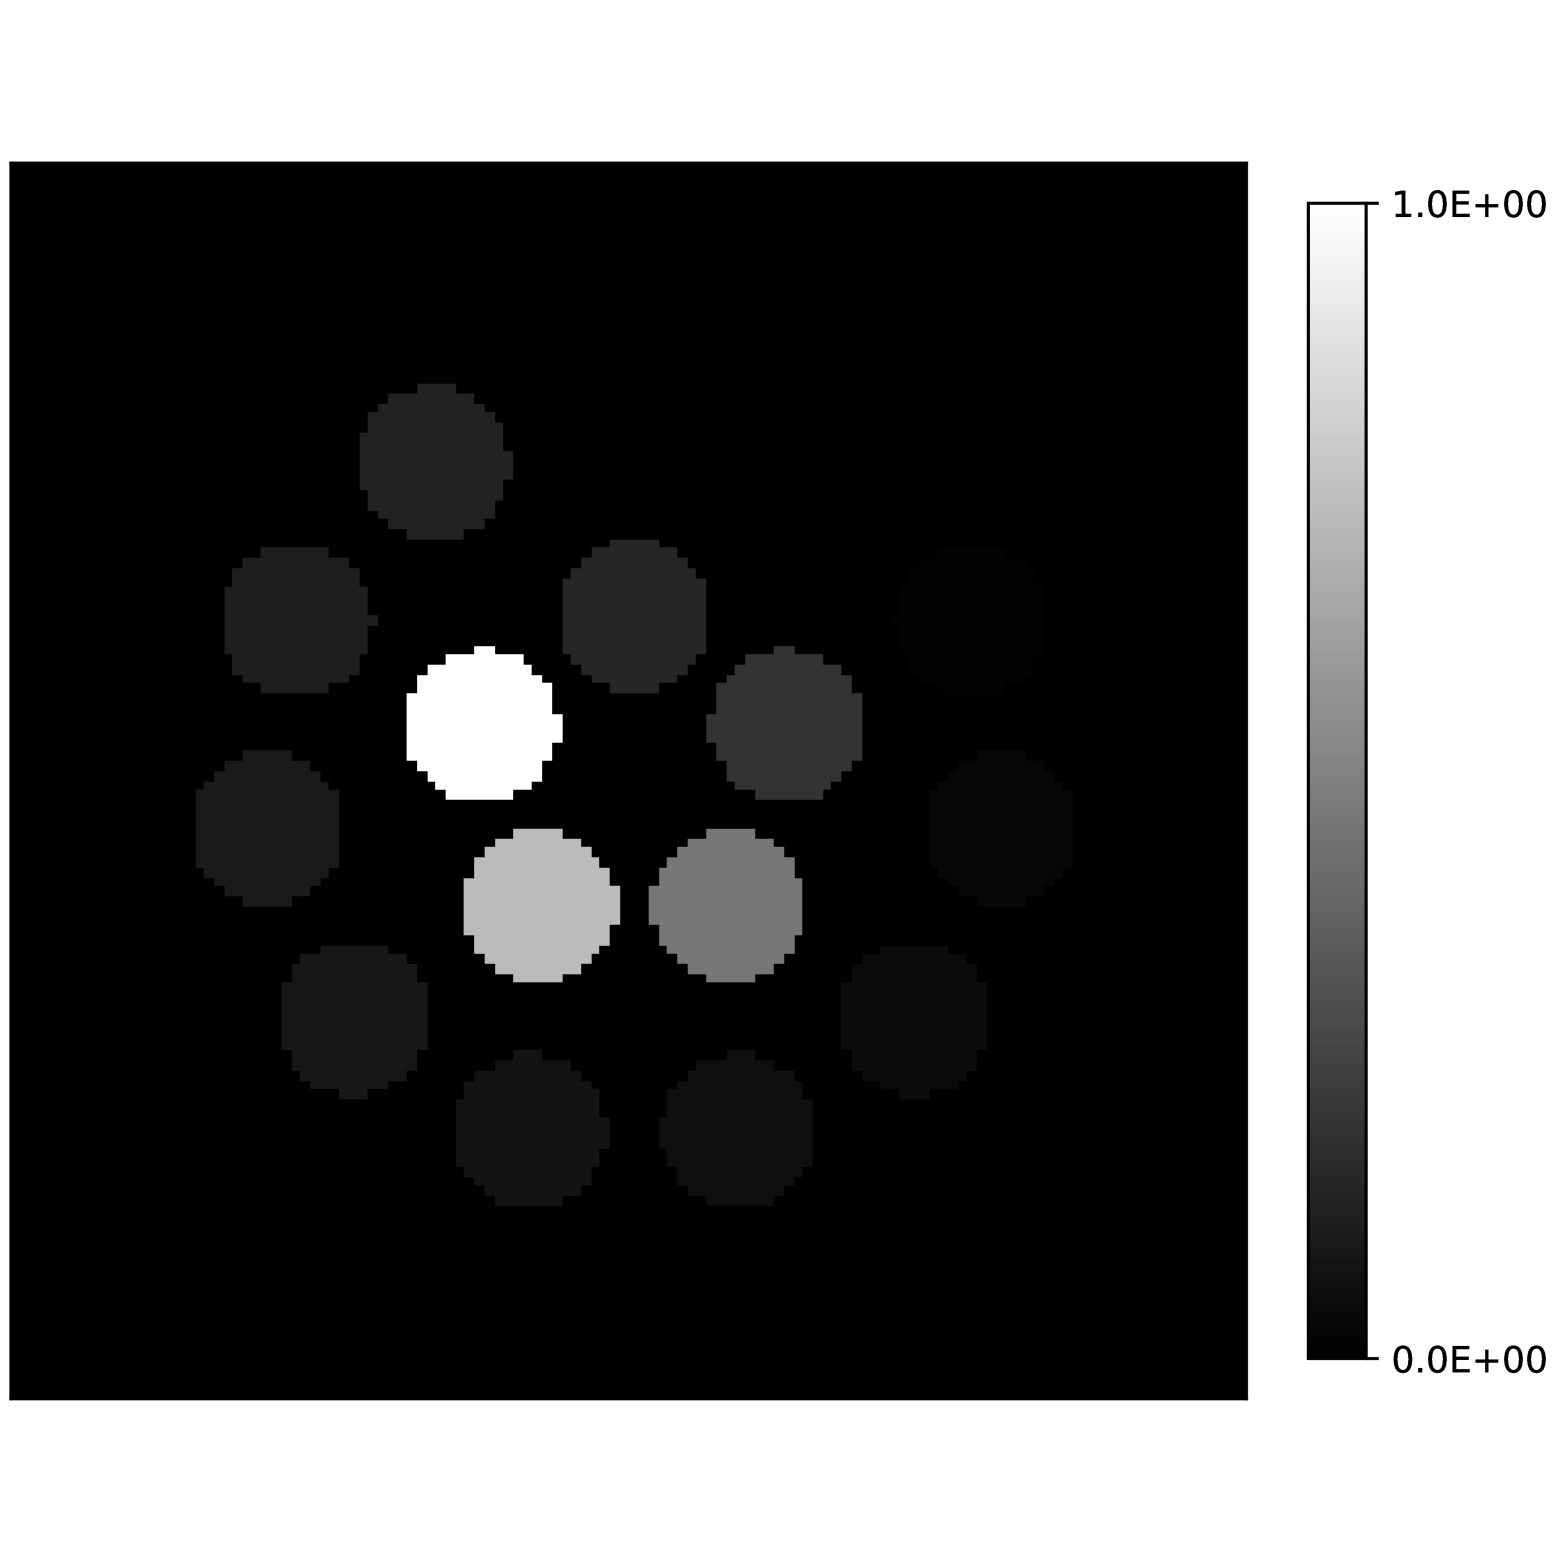

Our theoretical results show that generic concentrations and maps can be recovered exactly even when the fieldmap is not identifiable. To illustrate the impact of this fact, we perform a recovery experiment on a water (Fig. 2(a)), fat (Fig. 2(b)) and silicone (Fig. 2(c)) in silico phantom. The concentrations are all real. The values for the fieldmap and used to generate the signal are shown in Figs. 2(d) and 2(e). The echo times have the form where ms and ms with .

We solve (23) using projected gradient descent as initial iterate a vector with all components equal to one. Forward finite-differences were used to compute the gradient. The bound on the norm of the gradient is Hz at voxels with non-zero signal magnitude, and kHz at voxels with zero signal magnitude. This avoids imposing artificial constraints at voxels with no signal. The step size used is and the termination conditions

In Figs. 2(f), 2(g) and 2(h) show the recovered concentrations of water, fat and silicone, and Fig. 2(j) shows the recovered . These recovered quantities are all qualitatively similar to their true values. In contrast, Fig. 2(i) shows the recovered fieldmap, which differs from its true value. By comparing the errors in the recovered concentrations, we see that they are within a reasonable accuracy except in regions with a large magnitude for the fieldmap gradient, indicating a bound that is too small (Figs. 2(k), 2(l) and 2(m)). A similar behavior is seen in the recovered (Fig. 2(o)). The error for the recovered fieldmap tends to be larger outside the area of the phantom (Fig. 2(n)).